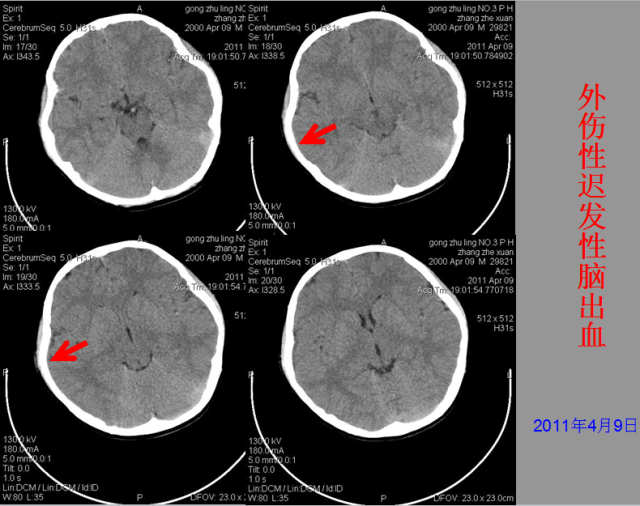

急性颅脑损伤篇

03